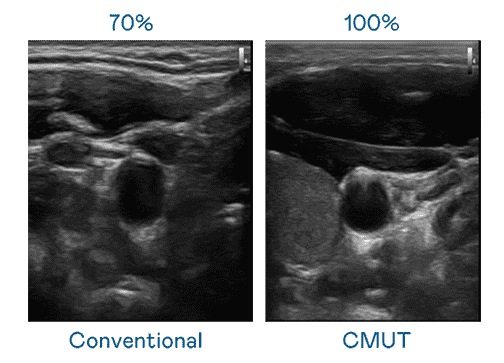

CMUT 技术是一种用电容式微机电元件来产生超音波讯号的技术。。。。与传统 PZT 压电式技术相比,,,,CMUT 频宽增加 30%,,更宽频的超音波讯号让影像解析度大幅提升,,,,是实现高影像品质医疗超音波扫描、、、促进精准医疗发展的关键技术。。。。

大频宽带来超清晰影像

超音波影像的解析度高低,,,首先取决于探头能发出的讯号频宽。。红龙扑克 CMUT 可提供高清晰的超音波讯号,,提供高频宽、、高灵敏度、、、影像纹理细节更高的超音波影像,,,,协助医护人员缩短影像判读时间及利用精准的医疗影像进行诊断。。。。